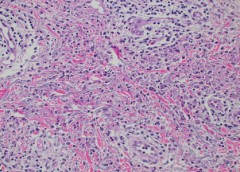

Researchers Uncover Clues to Why Some Wounds Don’t Heal